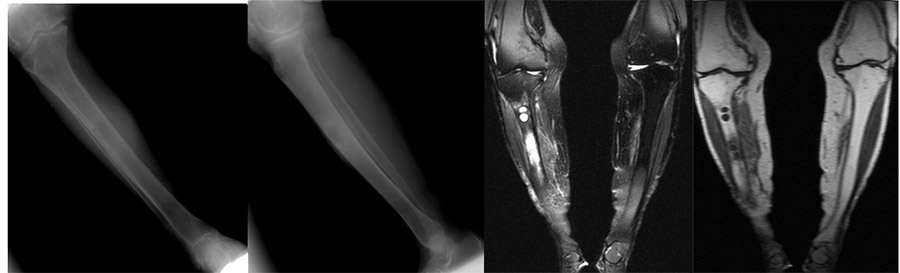

Before the surgery: X-ray and MRI show damage to the middle region of the right tibia due to metastasis and surrounding edema.